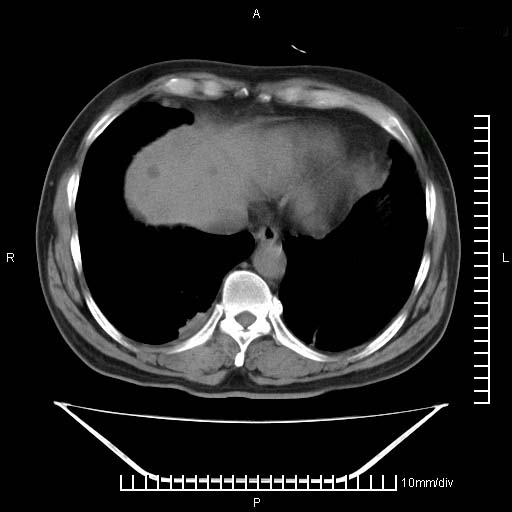

标题: CT25082:肝脏增强:男性,70岁 [打印本页]

标题: CT25082:肝脏增强:男性,70岁

患者以心脏疾病收住院,腹部无明显症状,b超查肝脏有占位。

增强效果不理想。考虑转移,胆囊壁明显增厚,不排除胆囊癌肝转移。

牛眼征,中心坏死无强化,外缘强化,最外缘又见低密度,考虑转移,与脓肿鉴别

考虑右肺下叶周围癌肝转移

肝内多发转移瘤,右下肺炎症并少量胸水。胃壁增厚建议胃镜,胰尾部“病变”为肠管。

1)肝脏多发性转移瘤(不排除胰尾癌转移所致可能)。2)腹水。3)右侧少量胸腔积液。

ct25082 结果:转移瘤

外院mr结果:胰尾恶性占位。